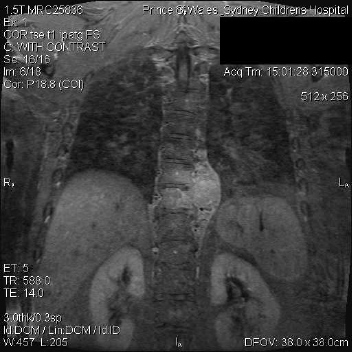

Cancer of the Spine

Cancer of the spine, both secondary and primary, are of particular interest to this practice. Dr Mobbs has undertaken further training in complex spine cancer surgery and reconstruction.

Click on the thumbnails for enlarged view